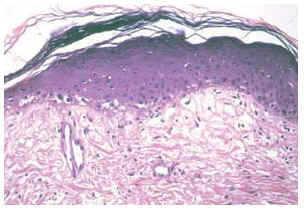

Asimismo, se realizó una biopsia cutánea de una lesión lineal de la región superior de la espalda (figs. 2 y 3).

Fig. 2.--Biopsia de una lesión lineal. (Hematoxilina-eosina, ×10.)

Fig. 3.--Detalle de los cambios histológicos. (Hematoxilina-eosina, ×40.)

El estudio histopatológico de una lesión lineal de la espalda demostró la presencia de una dermatitis de interfase, en forma de una vacuolización de la membrana basal y unos infiltrados linfocitarios de disposición perivascular en la dermis superficial (figs. 2 y 3).

En el estudio histopatológico se observa una dermatitis de interfase, es decir, una vacuolización focal de la capa basal junto con infiltrados linfocitarios perivasculares situados en la dermis superficial. Estos hallazgos son superponibles a los que se encuentran en las lesiones típicas de una dermatomiositis, lo que apoya la idea de que el eritema flagelado es, en realidad, una lesión cutánea más de esta enfermedad9.